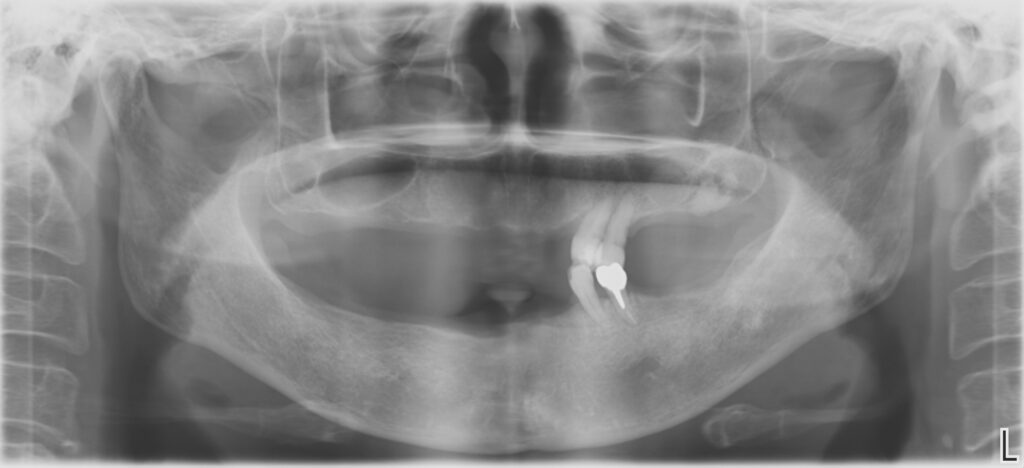

Before

治療期間・回数

約6ヶ月・約6回

費用

23,100,000円

治療のリスク

外科手術が必要になるため、患者様に体力的な負担がかかる。